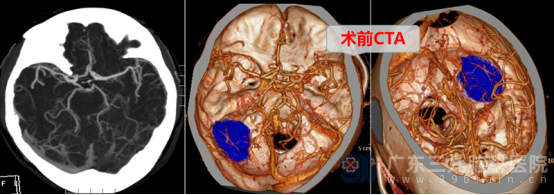

术前,神经外十科团队为患者完善头颅MR和CTA检查,进一步明确了病情。患者的后颅窝左侧枕部-左侧小脑幕下存在占位性病变,范围约40mm×30mm×37mm,考虑脑膜瘤可能性大,且局部与邻近左侧横窦关系密切,病变区还有少许血管影围绕及穿行,这给手术增加了不小的难度。